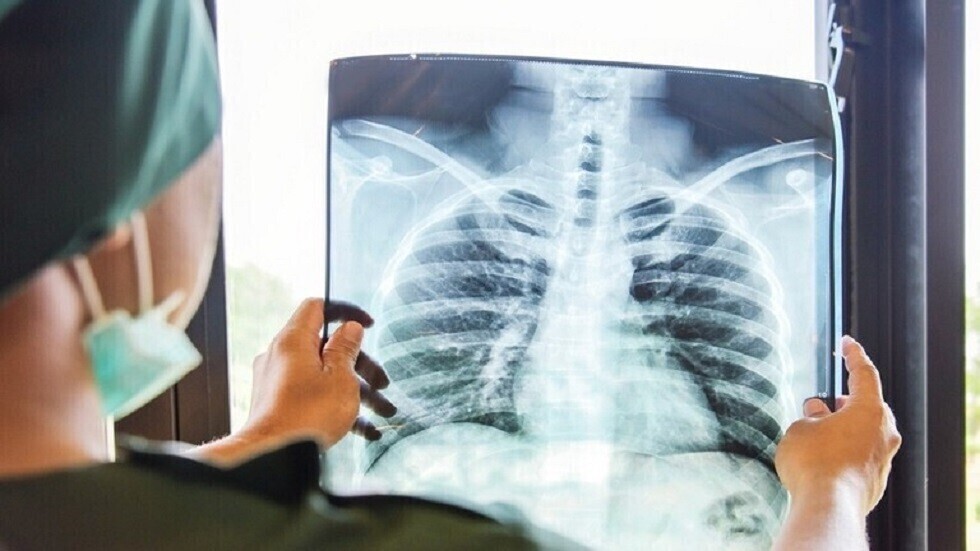

ما مدى خطورة الأشعة السينية على الصحة؟

أفادت الدكتورة أوكسانا بلاتونوفا أخصائية الأشعة، أن الأشعة السينية لا تزال أداة تشخيصية مهمة، ولكن لا تزال المخاوف تحيط بها.

وتوضح الطبيبة، لماذا قد يكون رفض الفحص أكثر خطورة على الشخص من الإشعاع نفسه.

ووفقا لها، يستخدم الإشعاع فقط في أنواع معينة من الفحوصات، ولا تتضمن جميع طرق التشخيص التعرض للإشعاع. فمثلا، يستخدم التصوير بالموجات فوق الصوتية والتصوير بالرنين المغناطيسي وهذه طرق آمنة تماما حتى للنساء الحوامل. أما الأشعة السينية فتستخدم فقط في التصوير الشعاعي، والتصوير الفلوري، والتصوير المقطعي المحوسب، بينما لا تتضمن طرق أخرى التعرض للإشعاع.

وتقول: "يمكن للنساء المرضعات الخضوع لأشعة الأسنان السينية، والتصوير الفلوري، وتصوير الثدي بالأشعة السينية بأمان. ولا يؤثر الإشعاع على حليب الثدي أو الطفل. ولكن توصف الأشعة السينية للنساء الحوامل فقط في حالات طبية صارمة، وحينها يجب حماية البطن بمئزر من الرصاص".

وبالإضافة إلى ذلك، تصدر الأجهزة الحديثة جرعات ضئيلة. أي لتلقي الإشعاع الضار، يتطلب الأمر الخضوع لمئات عمليات المسح المتتالية - وهو أمر مستحيل في الممارسة العملية. وللمقارنة، تصدر أشعة الأسنان السينية حوالي 30 ميكروسيفرت، وتصدر أشعة الفلوروغرافي (fluorography) حوالي 500 ميكروسيفرت، و تعتبر الجرعة التي تزيد عن 50 ألف ميكروسيفرت سنويا خطيرة.

الأشعة السينية تكشف عن الفرق الهائل الذي تحدثه لقاحات "كوفيد-19" حقا في الرئتين

وتشير الطبيبة إلى أنه لا أساس من الصحة للمخاوف الشائعة بشأن مخاطر أشعة الأسنان السينية. لأن الشعاع يركز بدقة على المنطقة المطلوبة، وتغطى الأنسجة المحيطة به.

وتقول: "الأشعة السينية هي إشعاع كهرومغناطيسي، مثل الأشعة فوق البنفسجية والضوء والحرارة. صحيح قد تلحق جرعاتها العالية الضرر بالخلايا، كالذي تسببه حروق الشمس. وأن الاستلقاء تحت أشعة الشمس على الشاطئ دون حماية أخطر بكثير من تصوير بالأشعة السينية للصدر مرة واحدة سنويا".

وتؤكد بلاتونوفا، أن عدم اكتشاف المرض أخطر بكثير من الخضوع للأشعة السينية، حيث المعدات الحديثة تقلل من المخاطر، كما أن الفحوصات في الوقت المناسب تسمح بالكشف السريع عن الأمراض وبدء العلاج.

المصدر: صحيفة "إزفيستيا"